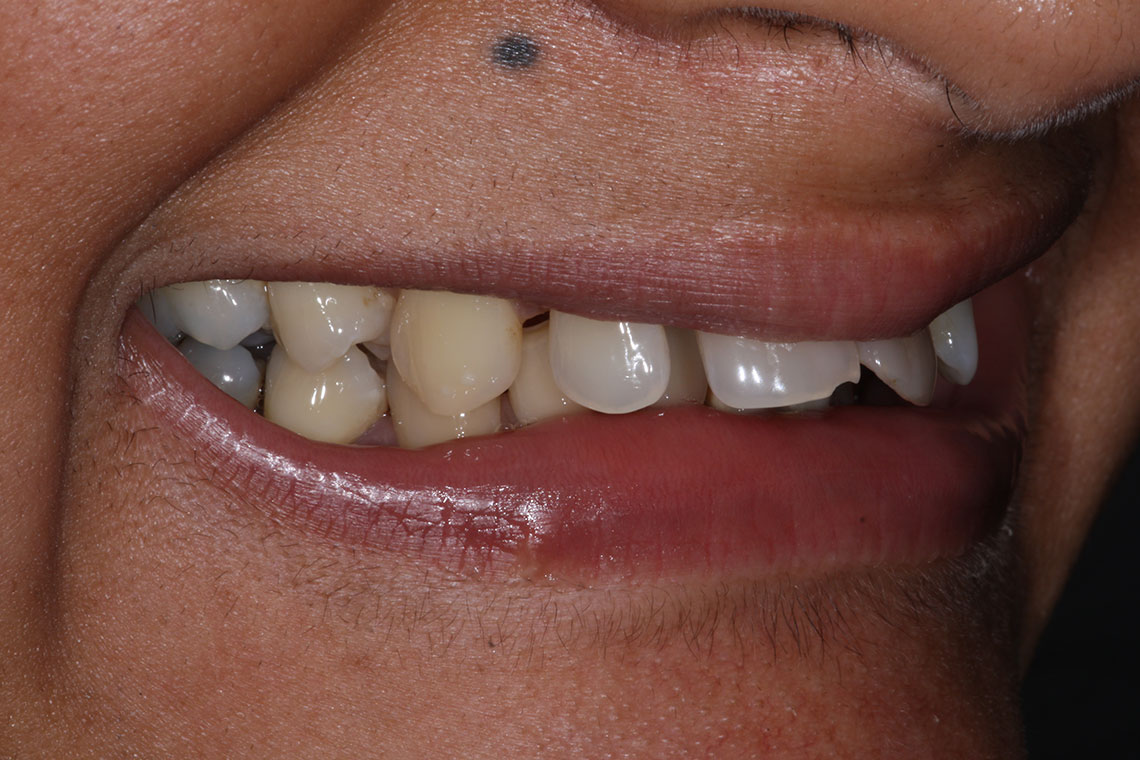

This lovely lady attended with very low confidence due to her teeth and smile. Gum disease and trauma had led to the teeth drifting. One of her front teeth was so loose that it needed to be replaced. We started by providing intensive treatment with our dental hygienist to treat the gum disease. Following this Invisalign® braces were used to align the teeth and the teeth were whitened. A dental implant was then placed to replace the loose front tooth and composite bonding was performed to the adjacent front tooth. The change in the patient’s confidence as a result of this work was breathtaking.